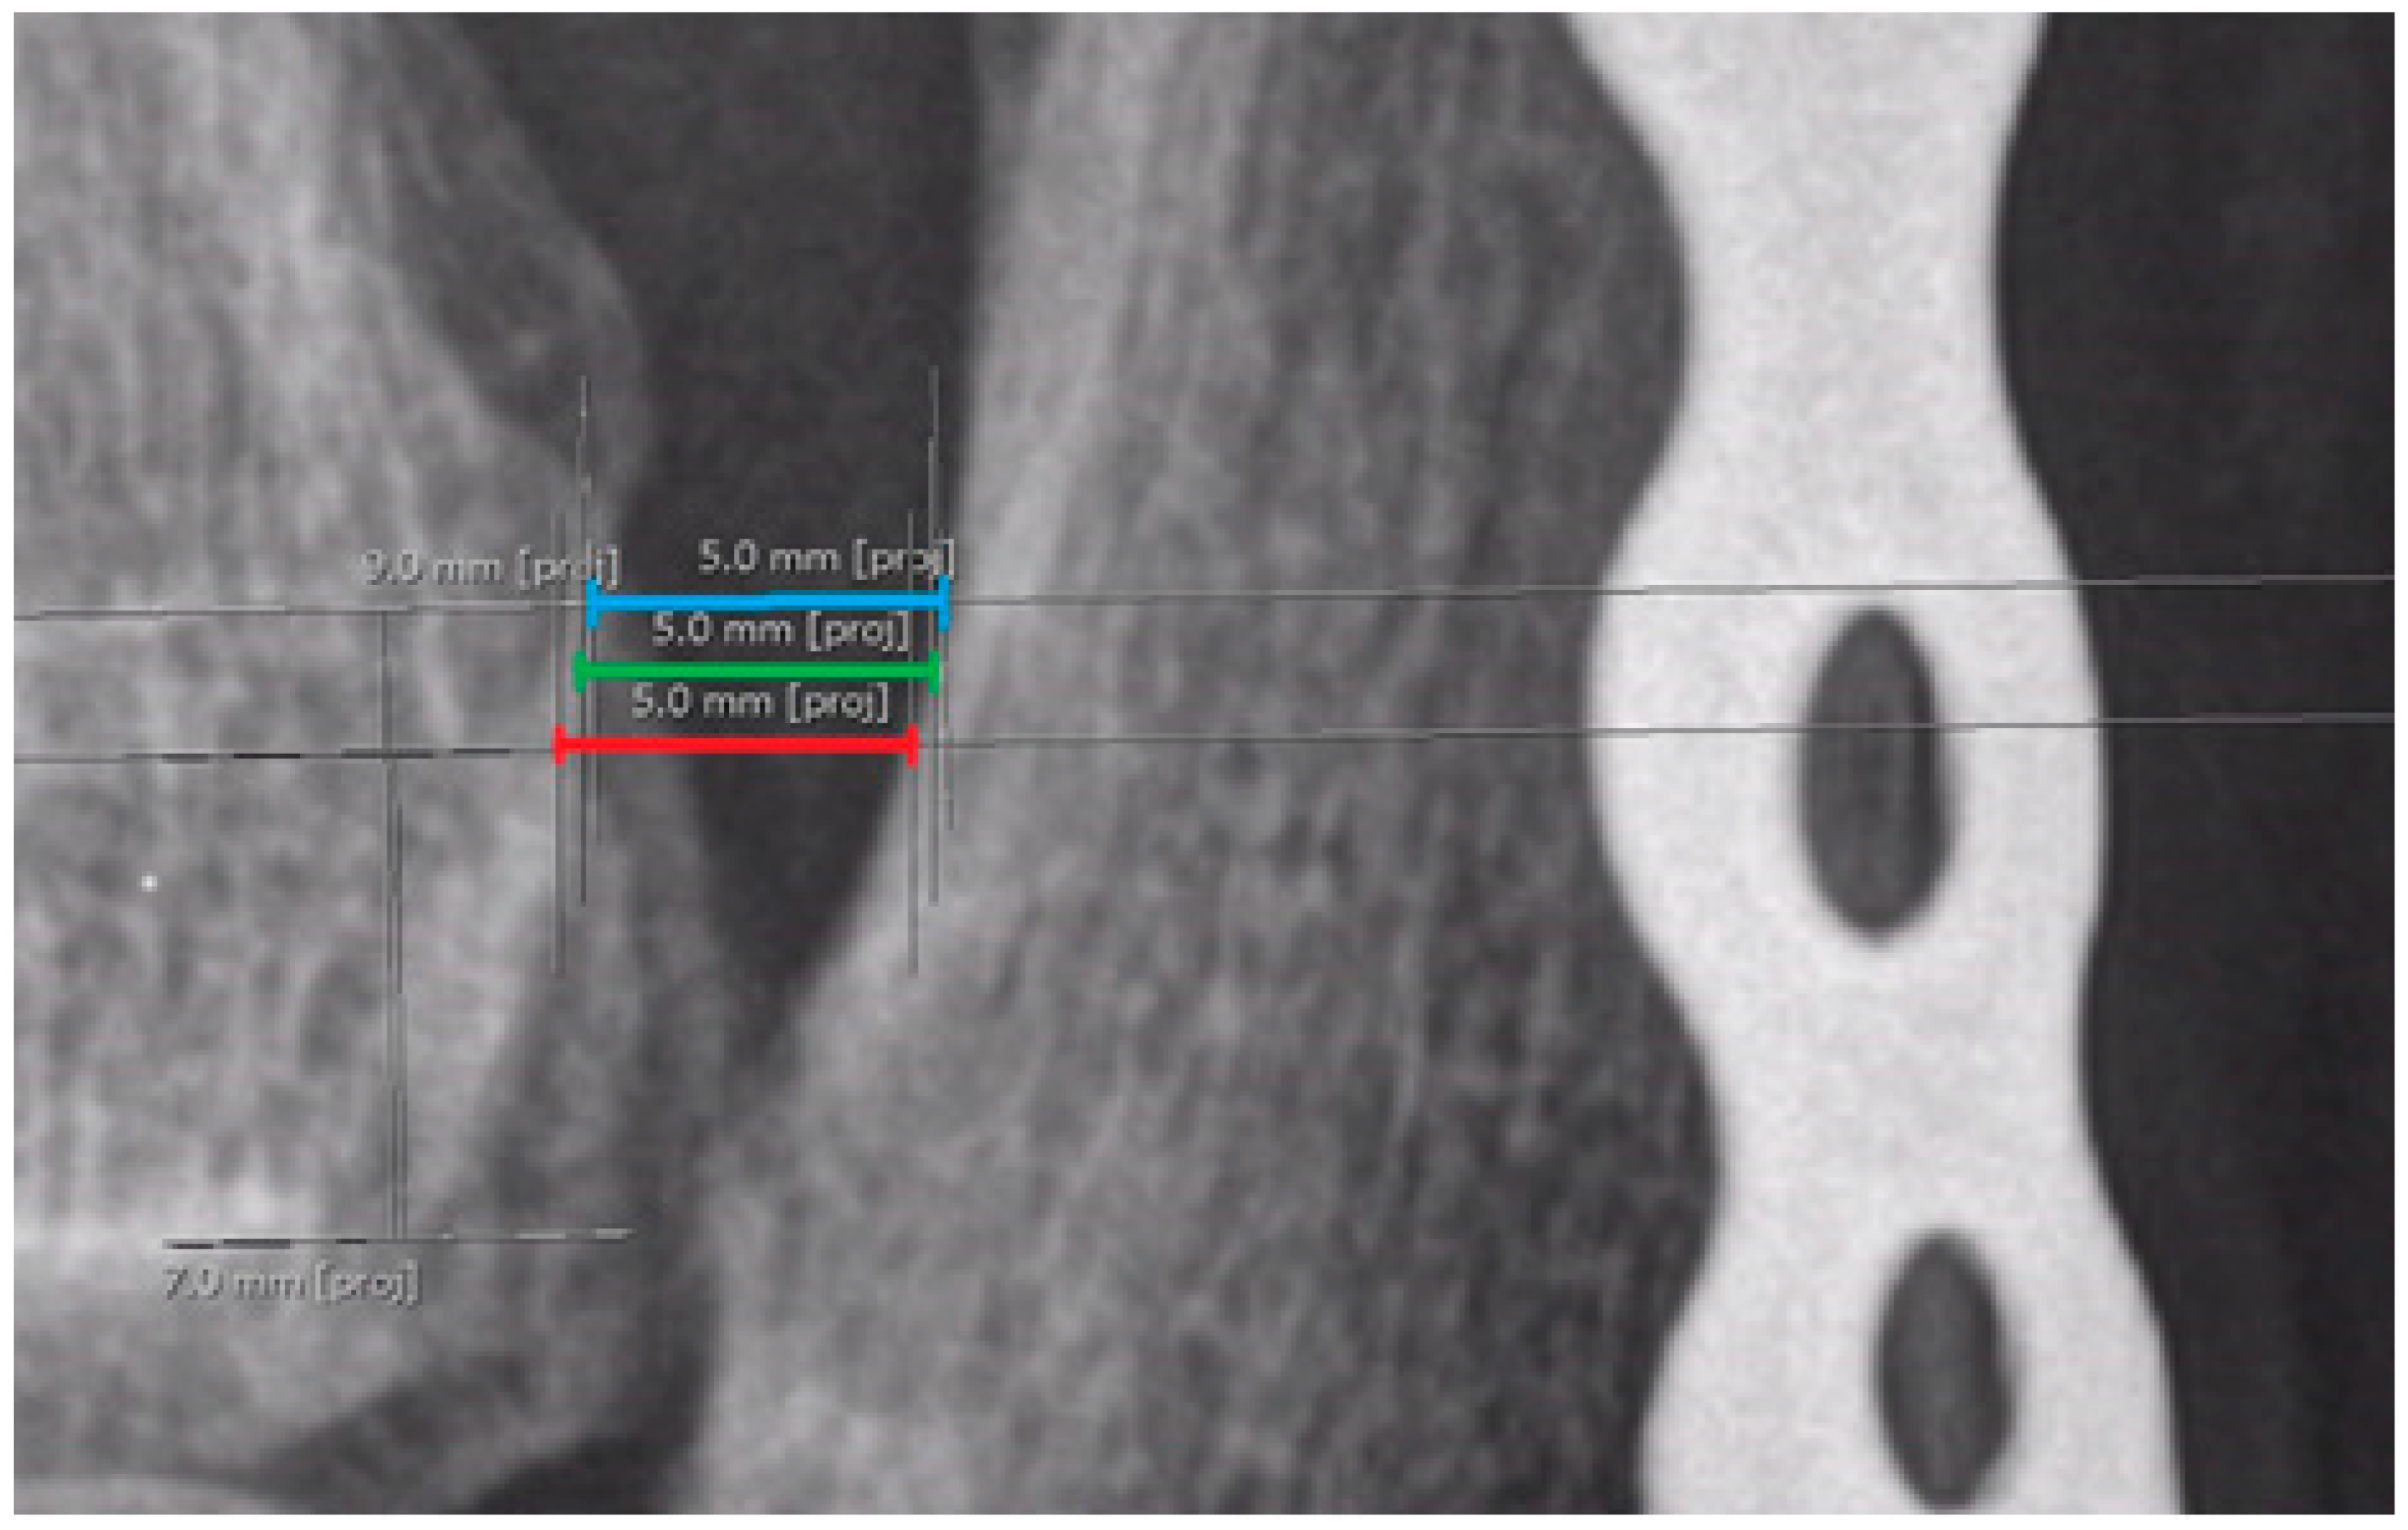

Ankle joint space—measurements taken from 3 different reference points on the tibial plafond (indicated in green in the figures below) (Figure 10);

2.

Medial clear space—measurements taken from 3 different reference points on the medial malleolus (indicated in blue in the figures below) (Figure 10);

3.

Lateral clear space—measurements taken from 3 different reference points on the lateral malleolus (indicated in red in the figures below) (Figure 10).

When it was not possible to obtain one of the measurements of the lateral/medial clear space (i.e., proximal or distal), the other two measurements were used, supplemented by one additional measurement in between;

Figure 10. Measurements without reference lines. The red, green, and blue lines represent measurements for lateral clear space, ankle joint space, and medial clear space, respectively. The exact values displayed in the figure are not essential.